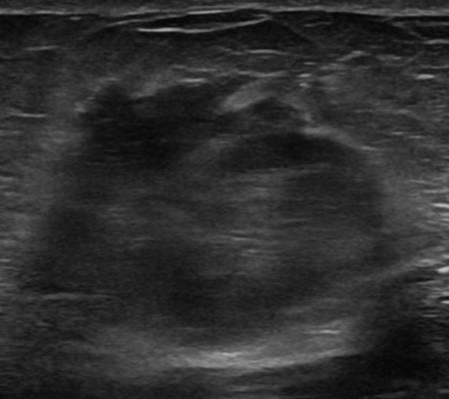

Ung thư vú

» Thông tin: Nữ giới – 76 tuổi.

» Lâm sàng: Khối tuyến vú.